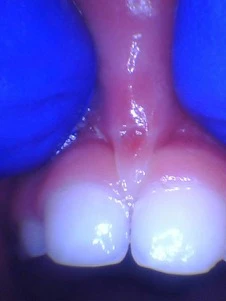

36 year old who was “clipped” as a baby. And after a proper release.

For a preschooler, it also is not a treatment strategy. Almost always when the child falls and rips the lip-tie, it only puts a small nick in the tissue (see below) and does not remove the tissue between the teeth. When we do it properly with the laser, all the tight tissue disappears, and then the teeth can properly close. There is now nothing to prevent the migration of the teeth toward the midline (mesial drift). Gap closure works best if done before 18mo old or when the permanent teeth are erupting.